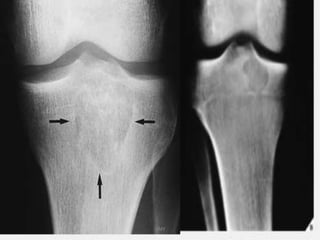

IMAGING

• X-rays

• epiphyseal

• well defined lytic lesions; either smooth or lobulated

margins with a thin sclerotic rim

• Internal calcifications can be seen in up to 40-60% of cases

• They range in size from 1-10cm, with most being 3-4cm at

diagnosis

• CT

• better delineation of the relationship to the growth plate

and articular surface

• Solid periosteal reaction (seen in up to 50% of cases) and

internal calcification (calcified matrix seen in ~ 1/2 of cases)

and cortical breach are also more easily appreciated.

• Endosteal scalloping may be seenUMY